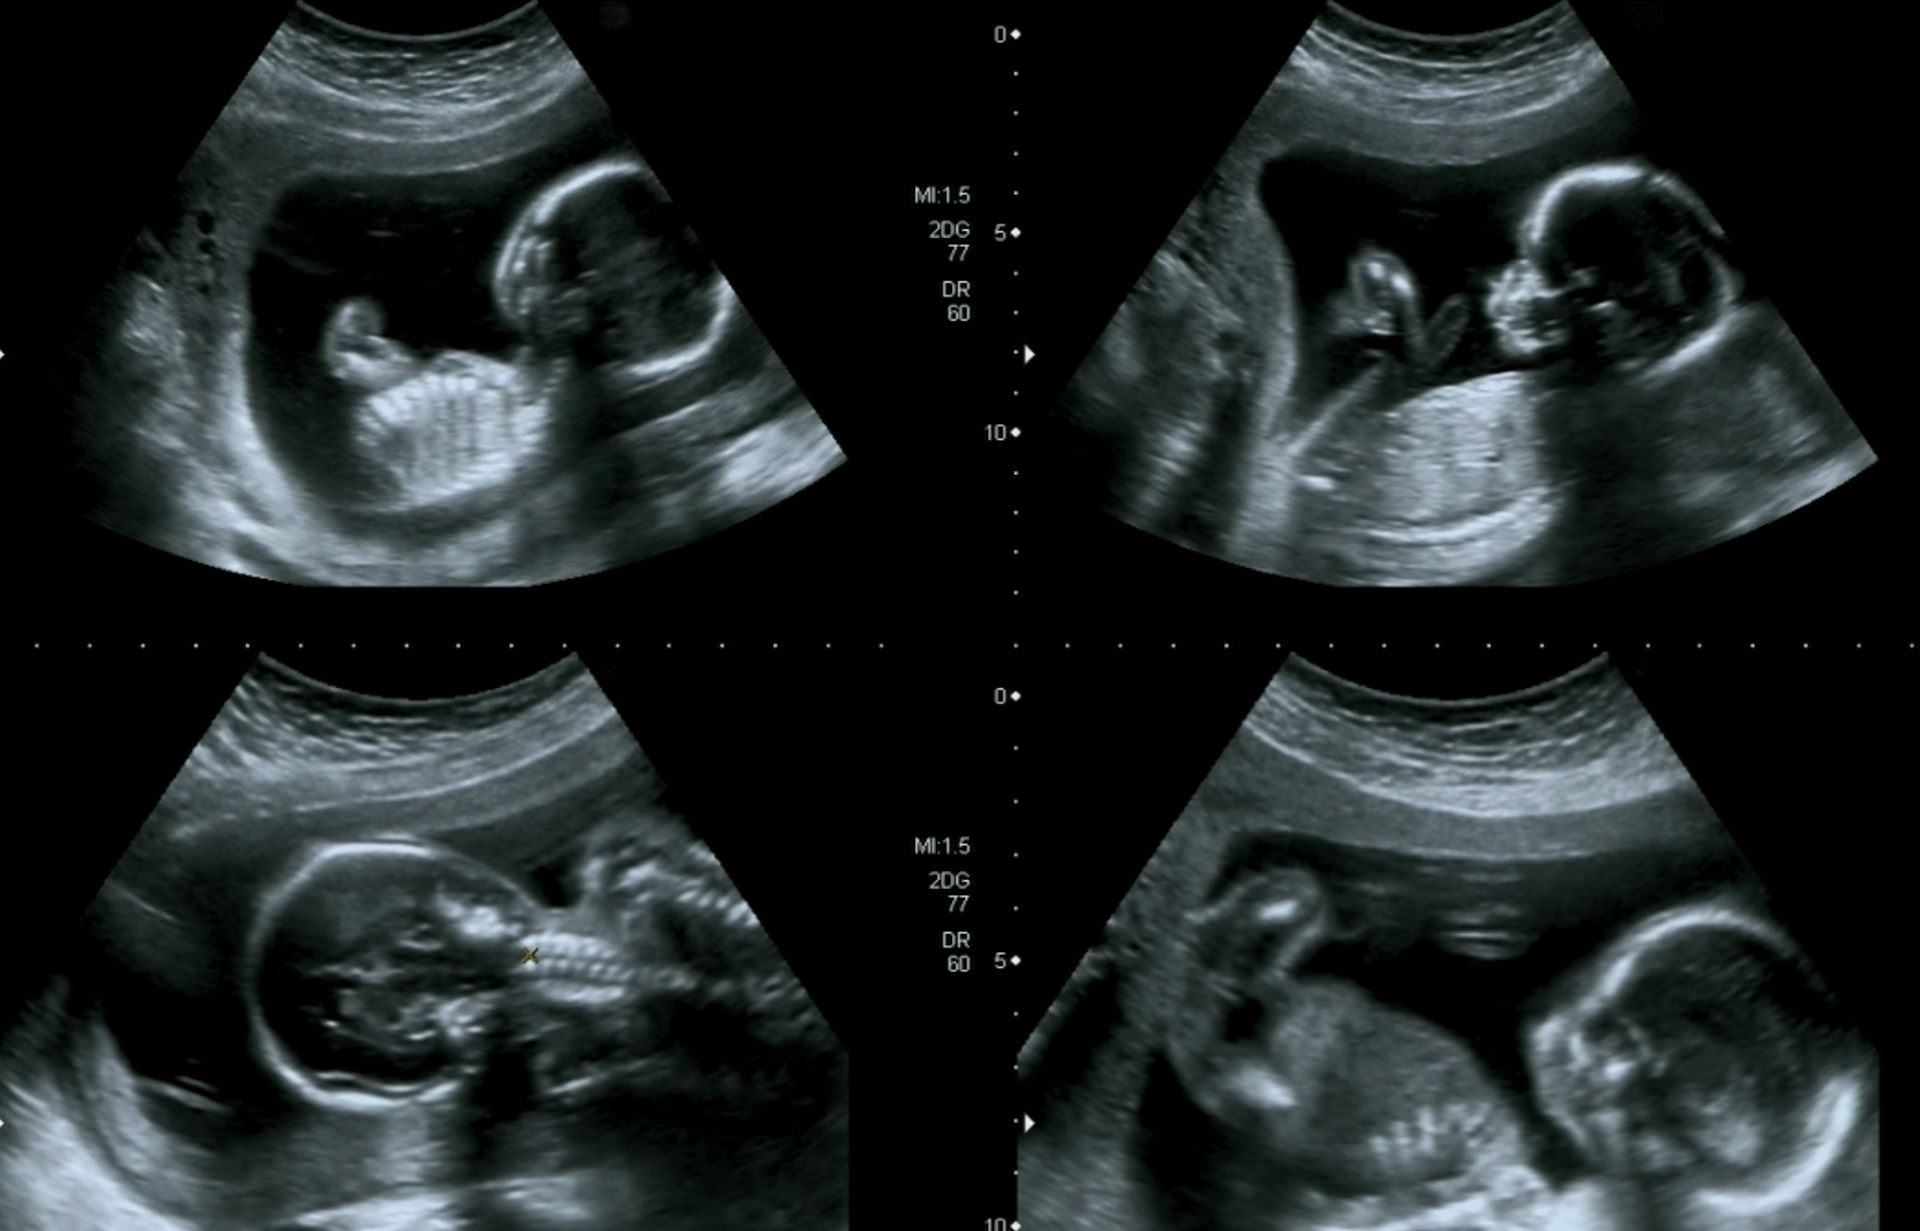

Ниже 19 недель беременности размер плода фото узи:

Ваше УЗИ во время беременности — это сканирование врожденной аномалии (CAS), которое также иногда называют сканированием врожденной анатомии или 20-недельным сканированием, проводится во втором триместре, между 18 и 22 неделями. Международное общество ультразвука в акушерстве и гинекологии (Isuog) рекомендует CAS осуществляться в рамках рутинного пренатального ухода за беременными всех женщин.

Это типичное 2D или 3D узи для проверки общего развития вашего ребенка.

Просто это более подробно помогает исключить аномалии роста «плода», такие как анэнцефалия (отсутствие сканирования верхушки черепа), пороки сердца и кишечные непроходимости, а также врожденные аномалии развития, такие как расщелина губы и расщелина позвоночника.